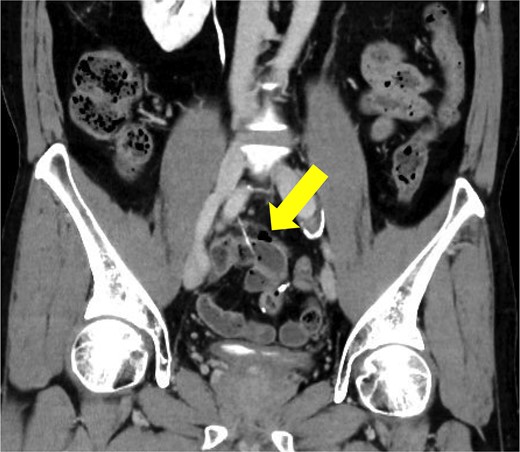

A male in his 40s was diagnosed with vEDS 5 years ago and has been followed up at our internal medicine department. His medical history included spontaneous mesenteric artery rupture and sigmoid colon perforation, for which he underwent two laparotomies. He presented to our hospital with a chief complaint of right lower abdominal pain. Physical examination revealed tenderness in the right lower abdomen without signs of peritoneal irritation. Laboratory tests showed slightly elevated inflammatory markers as follows: white blood cell count: 8000/μl, C-reactive protein: 6.51 mg/dl. Contrast-enhanced computed tomography revealed a foreign body in the ileum with bowel perforation (Fig. 1). Free air was localized in the mesentery and no abscess formation was observed. A detailed inquiry into the onset of abdominal pain revealed that he had consumed codfish 6 days prior. Based on these findings, the patient was diagnosed with a small bowel perforation caused by a fish bone. Although surgery for a patient with vEDS involves the risk of fatal complications, emergency laparotomy was performed due to the potential for injury to other organs or blood vessels and the risk of peritonitis from the migration of the fish bone. Intraoperative findings showed severe adhesions of the small intestine and a sharp 4 cm foreign body (fish bone) located 15 cm proximal to the terminal ileum penetrating the mesentery through the ileal wall (Fig. 2). We removed the foreign body and confirmed that it is a fish bone (Fig. 3). We resected ~5 cm of the small intestine, including the perforation site, and performed a stapled anastomosis. The patient developed postoperative paralytic ileus, which improved with conservative treatment using a nasogastric tube, and he was discharged on postoperative Day 27.

Contrast-enhanced computed tomography before surgery. A sharp foreign body with bowel perforation was identified in the ileum. Free air was localized in the mesentery and no abscess formation was observed.